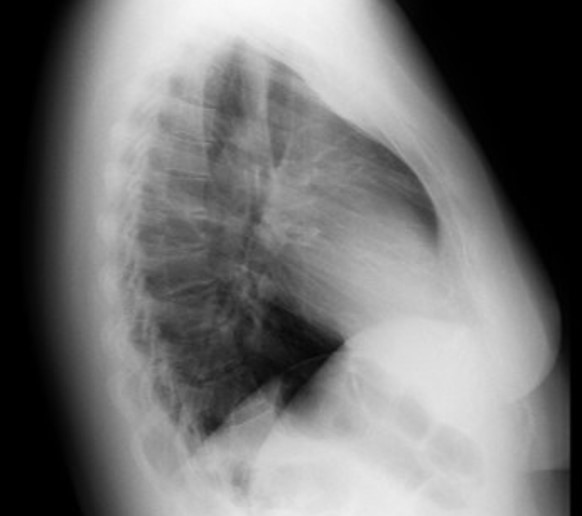

3. Radiografía de tórax: Parénquima pulmonar con hilios pulmonares aumentados de tamaño con visualización de vasos pulmonares que se extienden hacia la periferia. Dilatación del tronco de la arteria pulmonar. Botón aórtico no calcificado. A nivel del mediastino medio se aprecia aumento de la silueta cardíaca a expensas de crecimiento de aurícula derecha (expansión del borde cardíaco derecho hacia campo pulmonar derecho) y ventrículo derecho (ocupación parcial del espacio retroesternal en radiografía lateral). Senos costo-diafragmáticos libres. Ausencia de derrame pleural.